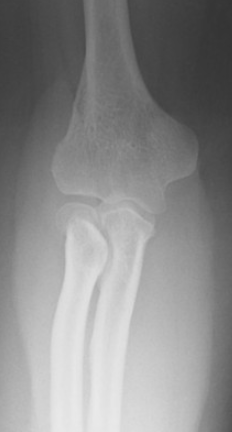

• Imaging Findings

• Basically any patella abnormality with likely recurrent patella dislocations

• Hypoplastic radial head/capitulum with likely recurrent elbow dislocations